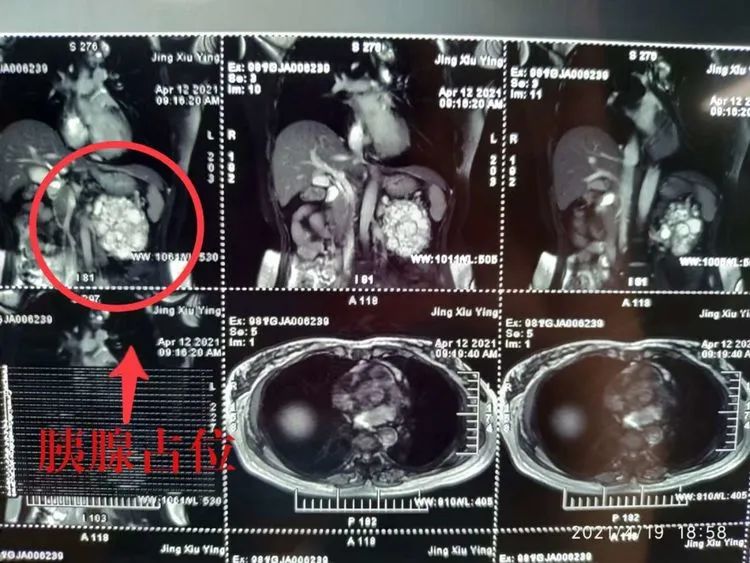

患者金女士,一月前在体检中发现了胰尾部占位。经朋友推荐,求诊于广济医院普外科顾冕主任。顾主任立即为其完善检查,触诊腹壁一10*6*10大小包块,CT提示:胰腺尾部占位,考虑为浆液性囊腺瘤,诊断为胰腺占位性病变。综合各项检查结果,顾主任团队为金女士拟定了“腹腔镜下根治性胰体尾切除术联合脾切除术”的治疗方案。经过家人的一致讨论,决定选择在广济医院普外科由顾主任为金女士主刀。